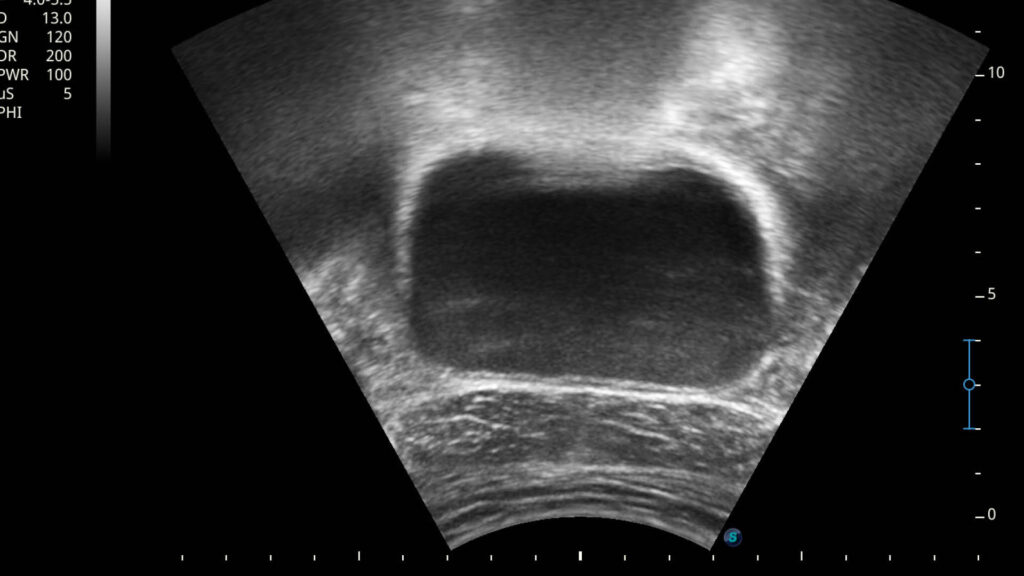

1. Visuelles Feedback in Echtzeit: Wolfgang Brunner-Fruhmann setzt einen Ultraschallkopf auf euren Damm-Bereich. Auf einem Bildschirm seht ihr live, wie sich die Muskulatur bewegt, wenn ihr den Beckenboden anspannt oder entspannt. Außerdem kann man dabei beobachten, wie sich auch die umliegenden Strukturen, wie zum Beispiel die Harnröhre bewegen und die Position verändern. Ein wesentlicher Faktor für die Kontinenz.

2. Präzision und Korrektur: Ihr erhaltet eine sofortige, visuelle Rückmeldung über die Qualität eurer Muskelaktivierung. Ist die Anspannung korrekt? Haltet ihr die Luft an? Spannt ihr zu stark oder zu schwach an? Kompensiert ihr mit anderen Muskeln? Der Therapeut kann euch sofort korrigieren und ihr seht euren Fortschritt auf dem Bildschirm.

3. Schnellerer Lernerfolg: Die visuelle Darstellung fördert das Körpergefühl und die neurologische Ansteuerung der Muskulatur immens. Was vorher abstrakt war, wird sichtbar. Das Gehirn lernt durch dieses klare Feedback deutlich schneller, die wichtigen Muskeln isoliert und effektiv anzusteuern.

4. Motivation und Kontrolle: Ihr seht eure Erfolge schwarz auf weiß bzw. in Graustufen auf dem Bildschirm. Das ist ein riesiger Motivationsfaktor und gibt euch ein Gefühl der Kontrolle über euren Körper zurück.

„Mit dem Echtzeit-Ultraschall nehmen wir unseren Patienten die Unsicherheit. Sie sehen, wie die tiefen Beckenbodenstrukturen arbeiten. Wir überspringen damit oft langwierige Phasen der reinen Wahrnehmungsschulung und kommen schneller zur effektiven Kräftigung“, betont Wolfgang Brunner-Fruhmann.